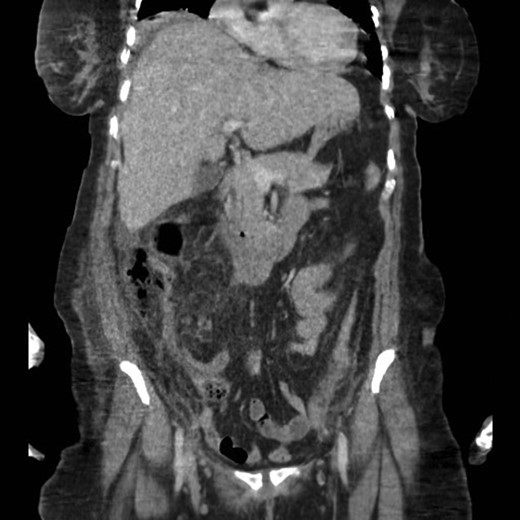

While in the ward, the patient accidentally removed her drains; a repeated CT scan showed well-defined enhanced collections in the right and left retroperitoneal spaces with evidence of the formation of a fat-pus level indicative of infectious fat necrosis.